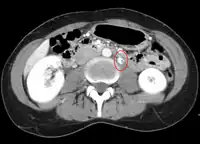

The nutcracker syndrome results from compression of the left renal vein between the aorta and the superior mesenteric artery.

The nutcracker syndrome (NCS) results most commonly from the compression of the left renal vein (LRV) between the abdominal aorta (AA) and superior mesenteric artery (SMA), although other variants exist.[1][2] The name derives from the fact that, in the sagittal plane and/or transverse plane, the SMA and AA (with some imagination) appear to be a nutcracker crushing a nut (the renal vein).

CT and MRI can be used afterward to confirm compression by the AA and SMA with comprehensive measurements of the abdominal vasculature. A "beak sign" can often be seen in CT scans due to the LRV compression. However, CT and MRI cannot demonstrate the flow within the compressed vein. These two modalities can be used to confirm other evidence for NCS such as back-up of blood flow into the ovarian veins.[11][6]